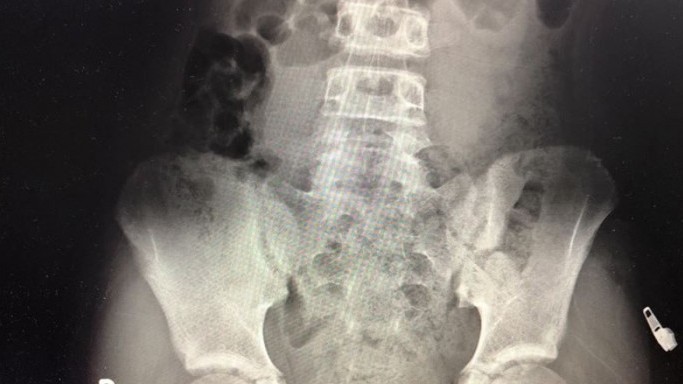

Bé gái nhét mặt dây chuyền vào vùng kín

Hướng dẫn nuôi dạy con -  14/01/2021

Bác sĩ Ông Huy Thanh, Phó giám đốc Bệnh viện Nhi đồng Cần Thơ, ngày 14/1, cho biết bệnh nhi nhập viện vài ngày trước. Phim chụp X-quang vùng bụng chậu...